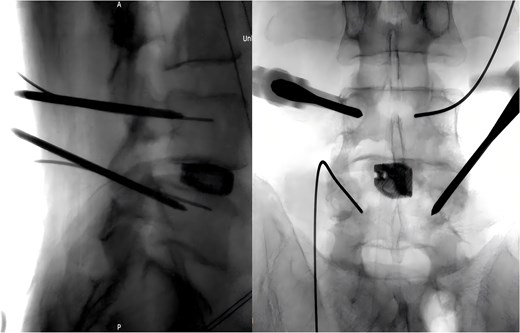

Following removal of the left L5 pedicle screw during the procedure, the smallest endoscopic sheath was inserted along with the endoscope to explore the screw trajectory. Under fluoroscopic guidance, endoscopic forcep was utilized to identify and grasp the fractured guidewire (Fig. 4). Tactile feedback of a metallic sensation confirmed precise localization. Approximately 6 mm of the fractured guidewire was successfully extracted (Fig. 5). Subsequent fluoroscopy confirmed complete removal of the broken guidewire. The left L5 pedicle screw was reinserted, and bilateral connecting rods were placed. The nuts were then securely fastened. Hemostasis was confirmed under endoscopic visualization, and the surgical incisions were closed and dressed with sterile coverings.